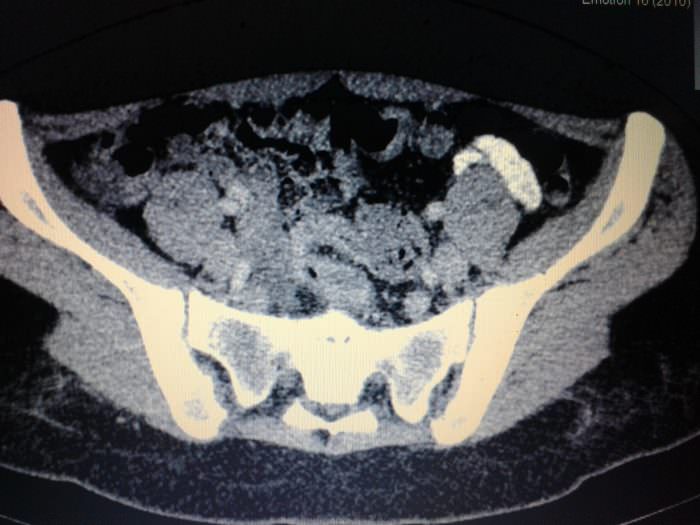

КТ малого таза – процедура сканирования внутренних органов для дальнейшей диагностики. Это точная процедура, помогающая информативно изучить органы малого таза.

Что показывает процедура? Компьютерная томография дает информацию о следующем:

- Есть ли воспаление органов.

- Наличие или отсутствие новообразований, а также опухолей (раковых и доброкачественных).

- Мочевой пузырь и его состояние.

- Последствия травм и ушибов в области таза.

КТ имеет такие же плюсы, как и МРТ, но назначается в случае невозможности провести магнитно-резонансную томографию. МРТ помогает лучше рассмотреть ткани внутренних органов, но не дает информации о костях. Поэтому для изучения мышц и остальных тканей лучше, по возможности, использовать магнитно-резонансную томографию, а если нужна информация более обширного характера – компьютерная томография.

КТ органов малого таза позволяет выявить и дифференцировать все объемные образования (кисты, опухоли, абсцессы), определить выраженность и распространенность воспалительного процесса, наличие жидкости, крови, гноя в малом тазу, определить характер врожденных аномалий, особенности строения органов, их размер и